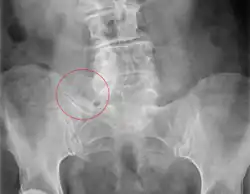

| X-ray of Bertolotti's syndrome (in this case, right transverse mega-apophysis of L5 with pseudoarticulation with the sacral ala). Woman 67 years old. |